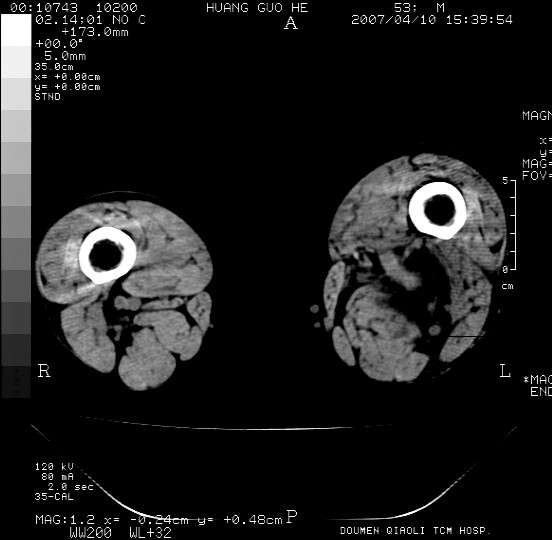

男性,左腘窝包块五个月,逐渐增大,疼痛功能受限,无发热。

查:远端血供差,质地硬。

左侧膝关节后国窝处略低密度软组织肿块,边界清楚,内见脂肪密度及高密度影.多考虑:软组织肿瘤_首选:脂肪纤维瘤.

左侧腘窝软组织肿块,边缘清晰,其内密度不均,周围骨组织无破坏,病灶增长较快,考虑:恶性病变(腘窝滑膜肉瘤可能),建议穿刺活检。